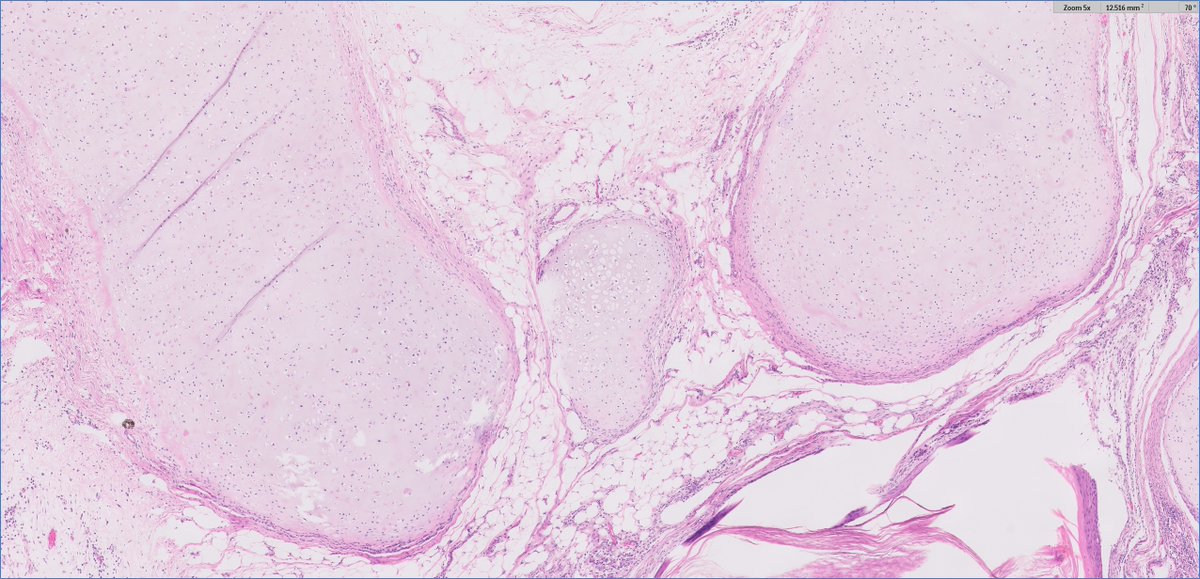

#GUpath orchiectomy for mixed GCT, rep sections shown here stage based on these 2 pics? ⏬poll to follow⏬